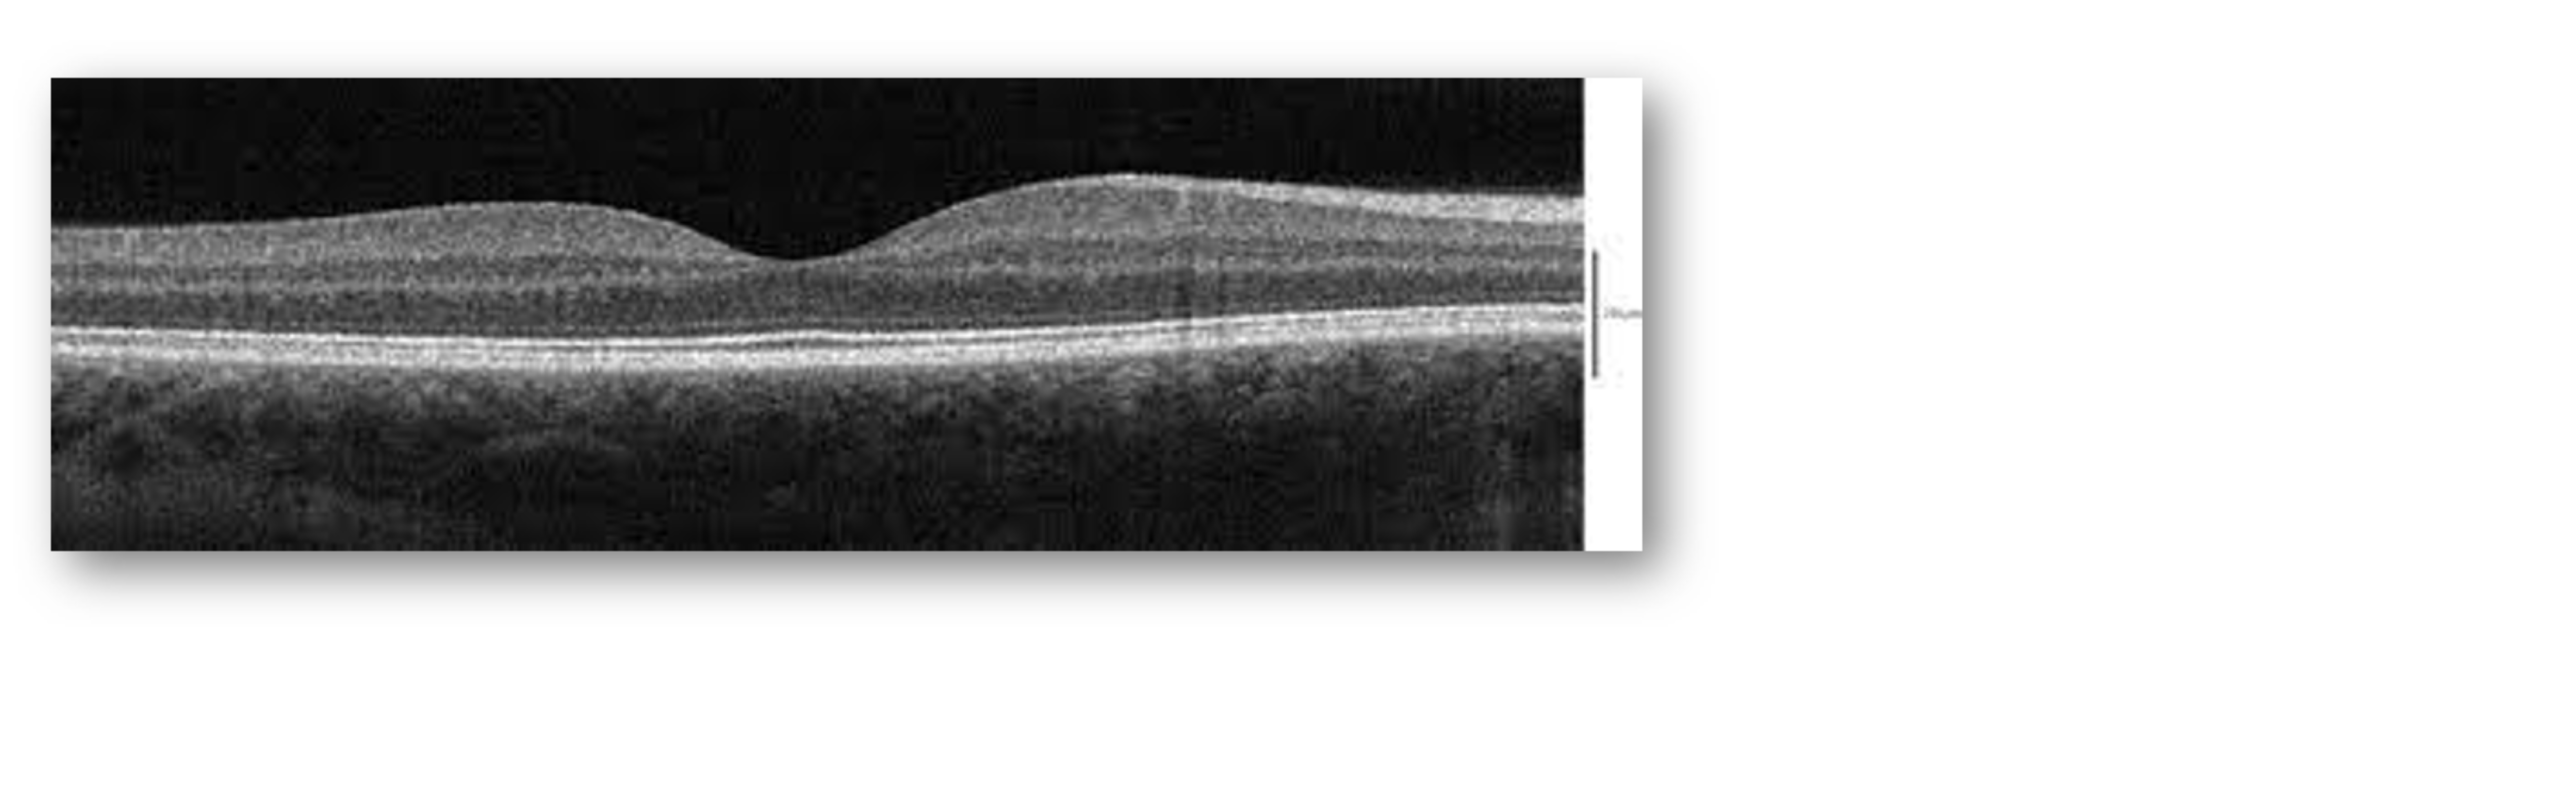

Despite the minimal NPDR depicted in the fundus photos and a normal OCT, we ran an OCT-A on the patient and found reason for concern in the left eye. Here, we noted significant patchy areas of non-perfusion and an irregular foveal avascular zone (Figure 3). That said, there was no evidence of intraretinal microvascular abnormalities (IRMA) or proliferative diabetic retinopathy (PDR). In cases like this, we want to learn as much as we can about the patient’s risk and therefore ran a baseline ERG next.

Figure 3: OCT-A